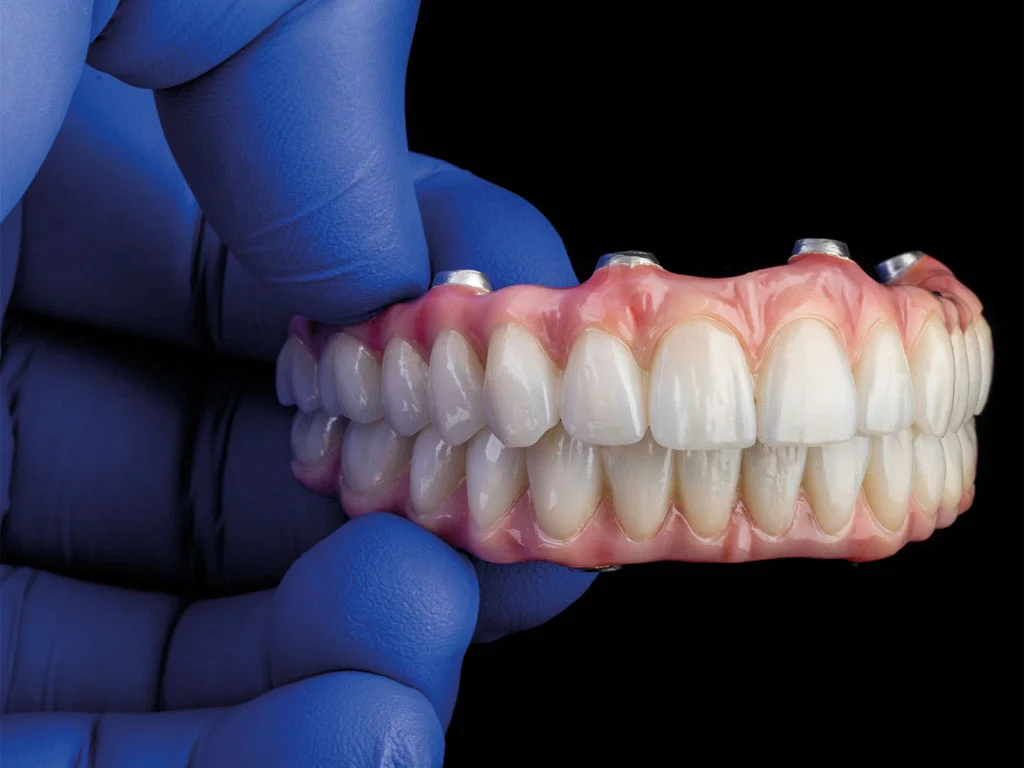

Geleneksel diş implant yöntemlerinde genellikle çene başına altı ila sekiz implant gerekirken, All on Four tekniği sadece dört implant kullanarak tam bir diş arkını destekler. Bu yerleştirme, kemik yoğunluğunu optimize eder, kemik grefti gereksinimini azaltır ve iyileşme süresini kısaltır. Arka implantlar genellikle açılı yerleştirilir, böylece protez için maksimum stabilite sağlanır. Bu süreçte titanyum alasim teknolojisi de önemli bir rol oynamaktadır.

All on Four implantlarının biyomekaniği, implant açısı ve protez üzerindeki yük dağılımıyla ilgilidir. Açılı arka implantlar, çiğneme kuvvetlerini eşit şekilde dağıtarak stres noktalarını ve olası implant başarısızlığını azaltır. Ön implantlar dikey destek sağlayarak protezi güvenle sabitler. Bu süreçte immediat yukleme (implant yerlestirildikten hemen sonra gecici dis takilmasi) de uygulanmaktadır.

Oral Implantoloji Dergisi’ndeki bir rapora göre, doğru protokoller uygulandığında All on Four implantlarının beş yıllık başarı oranı %95’in üzerindedir. Dijital görüntüleme, rehberli cerrahi ve CAD/CAM teknolojileri, hastaya özel tedavi planlarının tasarlanmasını sağlayarak daha yüksek hassasiyet sunar. Bu süreçte dental protez teknolojisi de önemli bir rol oynamaktadır.

Titanyum veya zirkonyum implantlar ve hassas mühendislikle üretilmiş protezler, mekanik arızaları minimuma indirir. Dijital tarama ve CAD/CAM üretim teknikleri, uyum ve yük dağılımını optimize ederek dayanıklılığı artırır.